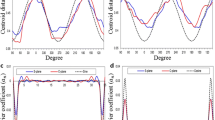

Radiomic features were extracted from each ROI and normalized with their maximum values. For each ROI, 17 intensity-based statistical features described the properties of the gray-level histogram and 14 morphological features described the geometric properties (Fig. 2). Textural radiomic features describing the local distribution of the image gray levels were not included in this study because they were considered not meaningful due to the small size of the ROIs.

Workflow Diagram. CT images were segmented in different regions of interest (ROIs). The radiomic features extracted from the entire sagittal suture (ROI_entire) were correlated to the skull shape severity. The dataset was split into training (80%) and testing (20%) sets. The training set was used for feature selection, model training and cross-validation. The testing set was used for hold-out validation. The features extracted from anterior (ROI_anterior), central (ROI_central) and posterior (ROI_posterior) sections of the sagittal suture were correlated to the post-surgical outcome. A logistic regression model was trained on a selected feature and validated via bootstrapping

In order to enhance the clinical translational value of the model, we dichotomized the Sloan post-surgical outcomes into two classes according to the excellent versus good/modest overall correction of the skull deformity: class 0 comprising the Sloan outcome I and class 1 comprising Sloan outcomes II, III and IV (Table 2; Fig. 2).

We performed a threefold cross-validation repeated five times for internal validation. The model performance was assessed in terms of area under the curve (AUC) of the receiver operating characteristic (ROC) curve. We set a threshold based on the prevalence of the outcome to compute accuracy, sensitivity and specificity for each repetition. The predictive value for the majority class 1, namely the positive predictive value (PPV), was also calculated. Then, we computed mean and standard deviation values of the metrics over the five repetitions.

We set the significance level at 0.05 with the aim to select only statistically significant features and build a logistic regression model. The model performance was evaluated by computing the AUC of the ROC curve and applying 2000 bootstrap resampling to obtain the 95% CI for the AUC.

A threshold based on the prevalence of the outcome was set to compute the sensitivity, specificity and the predictive value for the majority class 0, namely the Negative Predictive Value (NPV), for the model with the average coefficients. The 95% CI for the performance metrics was obtained with the Jeffrey’s method recommended for small sample sizes [17] (Fig. 2).

No statistically significant difference between the two classes of skull shape severity was found for the number (p value = 1) or for the position (p value = 0.96) of the fused sections (Fig. 3a–b).

Distribution of the fused sections for the dichotomized scaphocephalic severity. a, b Barplots indicating the number (a) and position (b) of the fused sections of the suture for the two classes of skull shape severity (class 0 dolichocephaly, class 1 hyperdolichocephaly). Distribution of the scaphocephalic severity for the dichotomized Sloan outcome. c Barplots indicating the clinical severity of the head shape (dolichocephaly, hyperdolichocephaly) for the two classes of Sloan post-surgical outcome (class 0 excellent, class 1 good/modest)

Similarly, no statistically significant association was found between the clinical severity based on the CeI and the binary post-surgical outcome (p value = 0.36) (Fig. 3c).

Boxplots (a) and density plots (b) of the dichotomized skull shape severity. a Boxplots of the feature F_stat.kurt extracted from ROI_entire for the two classes of skull shape severity; b distributions of gray levels (density plots) within ROI_entire for patients belonging to two classes of skull shape severity and characterized by F_stat.kurt values within the interquartile range (IQR)

Boxplots (a) and density plots (b) of the dichotomized Sloan post-surgical outcome for ROI_posterior. a Boxplots of the feature F_stat.kurt_post extracted from ROI_posterior for the two classes of Sloan outcome, b distributions of gray levels (density plots) within ROI_posterior for patients belonging to the classes 1 and 0 of Sloan outcome and characterized by F_stat.kurt_post values within the interquartile range (IQR). ROC curve of the logistic regression model built for ROI_posterior (c). 95% confidence intervals (CI) for the sensitivity and specificity are represented as bars

The predictor F_stat.kurt_post showed indeed a statistically significant estimated model coefficient with an AUC (95% CI) of 0.75 (0.61;0.88) (Fig. 5c).

The model coefficient estimates (95% CI) were as follows: − 1.66 (− 2.39; − 0.93) for the Intercept (p value < 0.001) and − 4.82 (− 9.18; − 0.45) for F_stat.kurt_post (p value = 0.030). From the bootstrapping, we obtained the following average (95% CI) model coefficients: − 1.73 (− 2.58; − 1.09) for the Intercept and − 5.19 (− 9.69; − 1.78) for F_stat.kurt_post. The corresponding model performance metrics (95% CI) were as follows: sensitivity of 0.82 (0.53;0.96), specificity of 0.64 (0.50;0.75), NPV of 0.95 (0.84;0.99) (Table 4). The NPV was high when compared to the null model, which was based on the prevalence of the majority class 0 (~ 0.83).